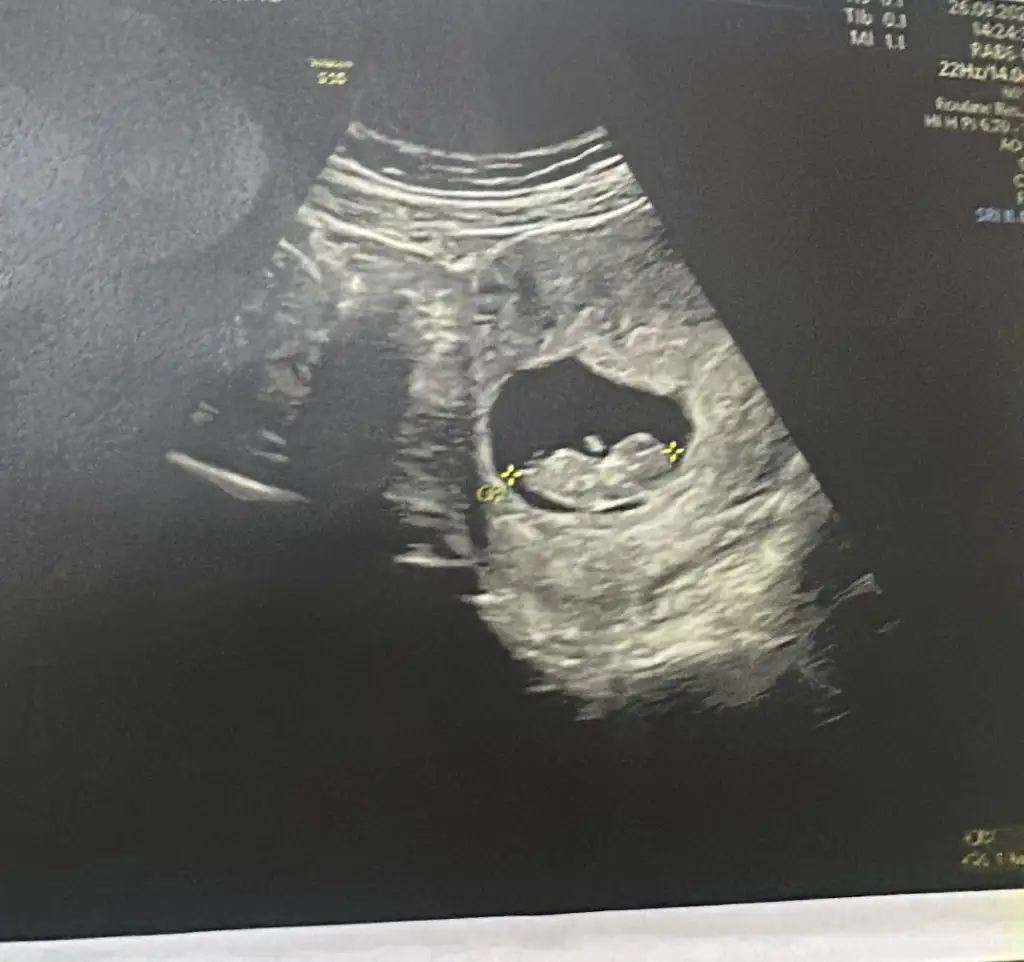

Cinsiyet tahmini

Ay bacak arası fotosunuda atayım 😂

Sizi heveslendirmek istemem hiç oğlum olmadı ama sanki erkek gibi duruyor bacak arasida rabbim gönlünüzdekini hayırlı eyleyip nasıl etsin inşaallah 💜